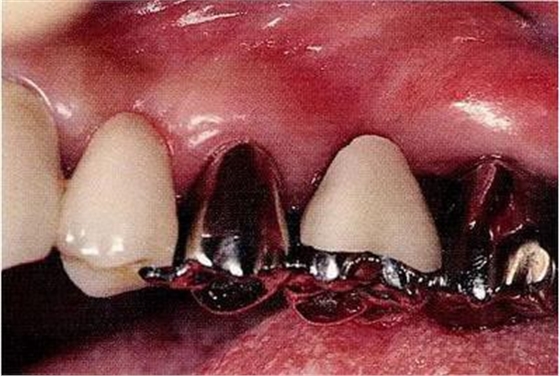

圖20-3將齦瓣剝離,完全去了除軟化牙質(zhì)的狀態(tài)。牙質(zhì)與骨緣處于相同的高度。

▼圖20-4

圖20-4為了得到生物學(xué)寬度,小心的使用車針沿著根面將骨質(zhì)切除。到達(dá)露出2mm健康牙質(zhì)的程度,已經(jīng)可以看到根面形態(tài)對(duì)于清掃已經(jīng)非常困難了。

▼圖20-5

圖20-5為了讓健全牙質(zhì)露出3mm,不得已將牙根分割。顎側(cè)牙根長(zhǎng)度不夠充分,所以判斷為無法保留。

▼圖20-6

圖20-6將顎側(cè)根拔除后,頰側(cè)根額側(cè)面形成了約3mm的平滑面。